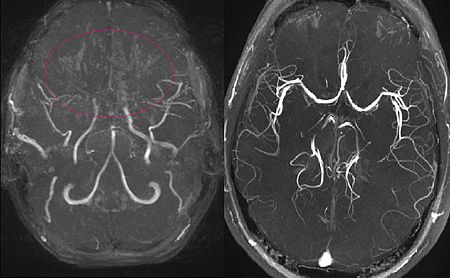

모야모야병은 뇌 기저부에 있는 주요 혈관이 점차 좁아지면서 뇌로 가는 혈류량이 줄어드는 질환입니다. 혈류가 부족해지면 뇌는 새로 가늘고 약한 혈관을 만들어 혈류를 보완하려고 하는데, 이 혈관들이 모여 있는 모습이 연기처럼 보여 ‘모야모야’라는 이름이 붙었습니다.

이 질환은 소아와 성인 모두에게 발생할 수 있으며, 연령대에 따라 나타나는 증상의 양상이 조금씩 다르게 나타납니다.